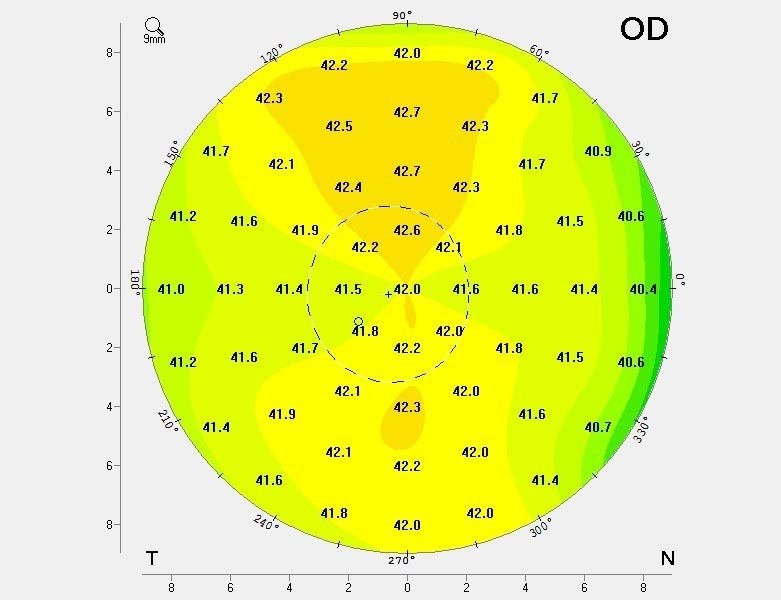

Eine normale gesunde Hornhaut ist glatt und zeigt eine gleichmässige Dicke. Die Form der Hornhaut ähnelt einem Ball, mit einer identischen Rundung in alle Richtungen.

Die Hornhaut ist in eine Richtung stärker gekrümmt als in die andere. Dreidimensional sieht die Hornhaut aus wie ein Ei. Diese Form verzerrt die Sicht, kann aber mit einer Brille problemlos korrigiert werden, da die Verzerrung symmetrisch ist.